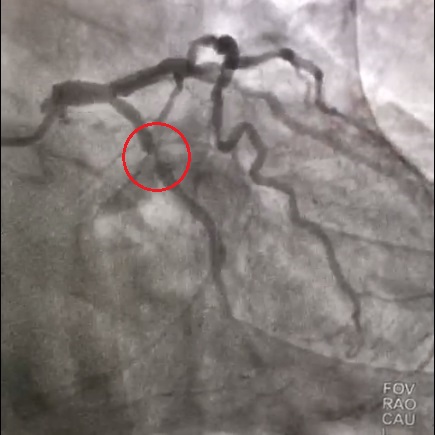

В отделении рентгенэндоваскулярных методов диагностики и лечения Всеволожской КМБ была выполнена экстренная коронарография, которая показала, что несмотря на восстановление кровотока по артериям сердца, имеются критические сужения в правой и огибающей коронарных артериях.

Результаты коронарографии